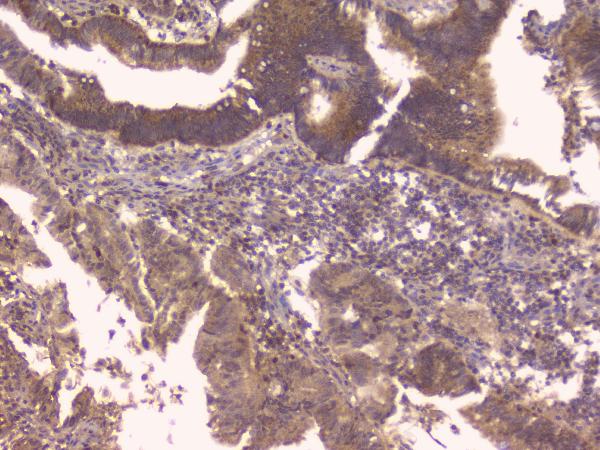

IHC analysis of OPG/TNFRSF11B using anti-OPG/TNFRSF11B antibody (A00863).

OPG/TNFRSF11B was detected in a paraffin-embedded section of human placenta tissue. Biotinylated goat anti-rabbit IgG was used as secondary antibody. The tissue section was incubated with rabbit anti-OPG/TNFRSF11B Antibody (A00863) at a dilution of 1:200 and developed using Strepavidin-Biotin-Complex (SABC) (Catalog # SA1022) with DAB (Catalog # AR1027) as the chromogen.